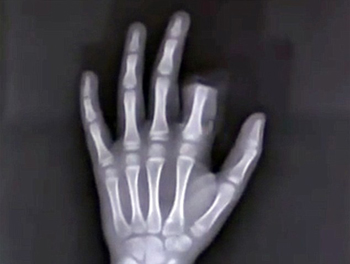

Haridwar, Oct 27: A 60-year-old man allegedly chopped off a finger of an eight-year-old dalit boy in Haridwar district when the latter inadvertantly stepped over a row of cowdung cakes kept for drying while playing with his friends.

Ramesh cut off the little finger of Aryan's left hand in a fit of rage as the boy unknowingly stepped over and messed up the row of cowdung cakes kept by him outside his house, Luksar police station incharge Dinesh Kumar said.

The matter came to light when the boy's father Rohtas Kumar rushed to the police station along with the boy and his chopped off finger immediately after the incident and registered a case against Ramesh Kumar and his 24-year-old son Shubham.

The child was then rushed to the district hospital from where he was discharged after stitches being applied to his wound.